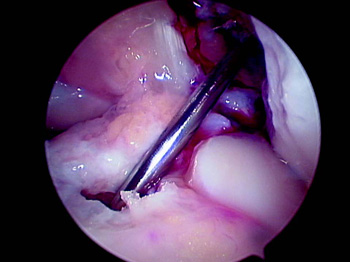

Creemos que el gran aporte de la cirugía con doble banda ha sido analizar el control rotacional, hecho que podemos lograr con una banda al reubicar la inserción femoral en un punto más a las 3 o a las 9 del reloj horario, existen muchas publicaciones que lo avalan (19, 20, 21). Musahl (22) muestra en su estudio que los túneles femorales dispuestos en forma más horizontal aportan mejor control rotacional. La tendencia actual es ubicar el túnel femoral más horizontal, remedando la huella de inserción del LCA, lo cual se puede lograr utilizando un portal anteromedial, que en nuestra experiencia utilizamos poco, como también medializando el túnel tibial y redirec-cionándolo con una dilatación mínimo de 2 mm (Fig. 1). Con esto logramos llegar de una forma más horizontal a la pared femoral obteniendo así un mejor control rotacional. (Figs. 2 y 3).

| Figura 1: Visión artroscópica de la redirección del túnel antes de la dilatación, apoyando la aguja guía en la pared lateral del túnel tibial. |